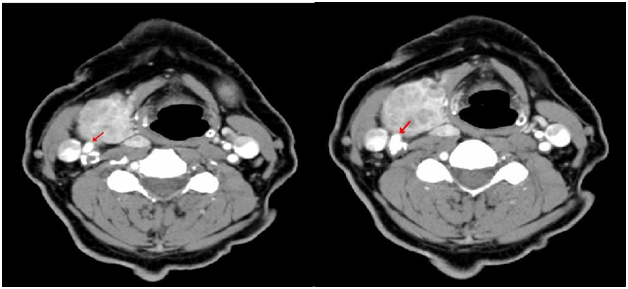

Upon further questioning it was found that the patient’s symptoms were always precipitated by turning his head to the right side…!! “When he was on vacation the spells occurred while he was looking out the window to the right; whereas at home after running up stairs there was a sharp right turn.” Therefore there was a high suspicion that a neck mass is compressing the carotid sinus causing a reflex bradycardia. Consequently a CT neck was performed that revealed a large goiter compressing on adjacent structures including the right carotid sinus (Figure 3 & 4).

Figure 3 Compression on the right carotid sinus (Right image) and on carotid artery bifurctation (Left image).